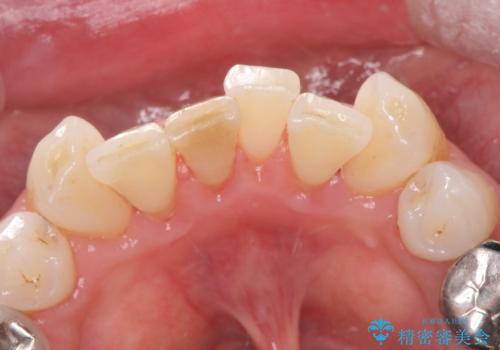

着色を綺麗に落とせました。

表面をツルツルに仕上げることで着色や汚れが付きにくくなります。